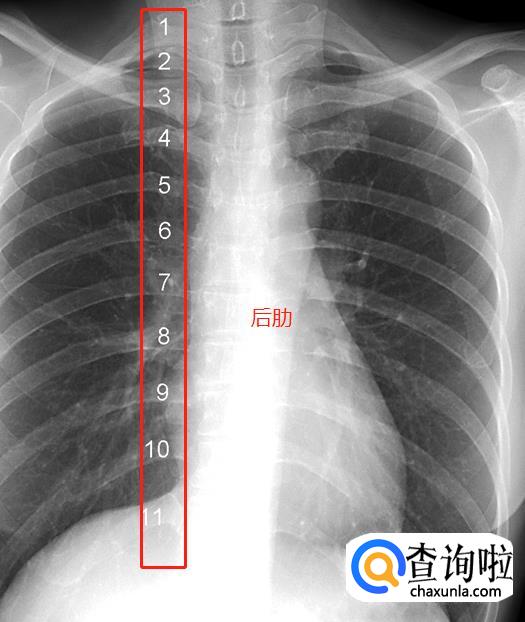

肋骨。一根肋骨在正位胸片上投影的前后端并不在同一水平,为了便于描述,肋骨被人为的分为后段(后肋)和前段(前肋)两个部分。后段通常是肋骨从胸椎到肺野外缘的投影,走行大致水平或略向外下倾斜。前段从肺野边缘起向内下呈比较大角度的斜向走行,越是接近第11、12肋的肋骨,其前段向下倾斜的角度越大。图中1~11分别标示第一到第十一后肋。